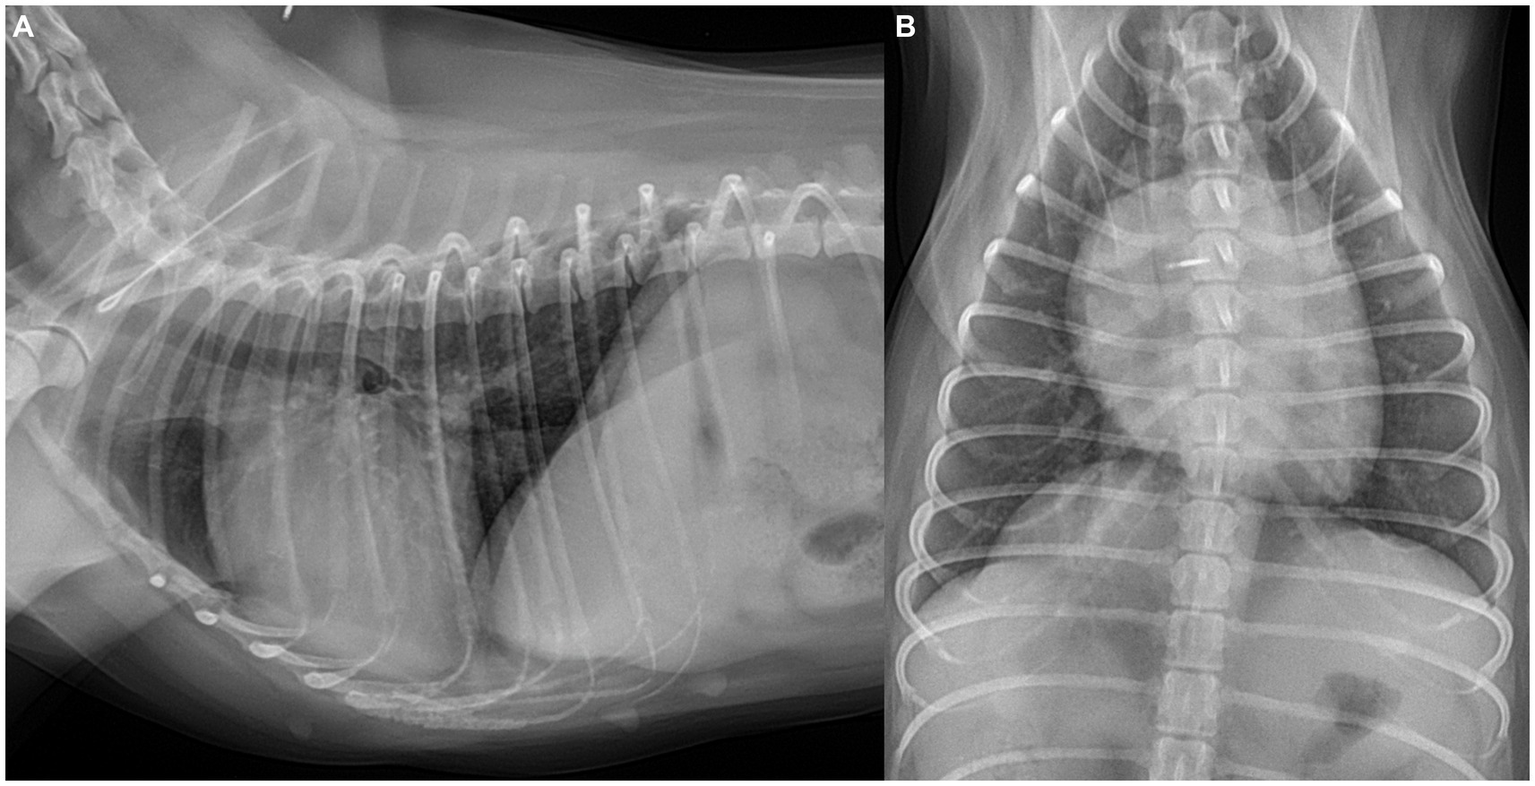

Thoracic radiography (DRGEM, Seoul, Republic of Korea) demonstrated a cardiac silhouette within normal limits, with a vertebral heart size of 10.8 (reference range: 10.69 ± 0.62) and a vertebral left atrial size of 2.1 (reference range: 2.17 ± 0.26) (11). Pulmonary vessels appeared normal, as the cranial lobar pulmonary vessels measured less than 1.2 times the diameter of the proximal third of the fourth rib, and the caudal lobar vessels did not exceed the ninth rib thickness (12) (Figure 1).

Figure 1. Thoracic radiographs of the dog. (A) Right lateral and (B) ventrodorsal views. Radiographs revealed a cardiac silhouette within normal limits, with the pulmonary vessels and caudal vena cava also measuring within normal limits.